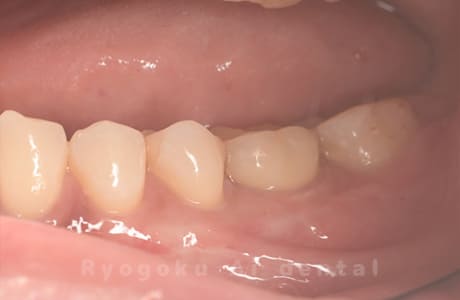

Case10

-

術前

術後

- 原因

- 左下6番欠損

- 治療内容

- インプラント治療

- 治療費用

- 約600,000円

左下の奥歯に歯を入れて欲しいとのことでご来院された患者様です。インプラント治療が最適とご提案させて頂き、治療を行いました。経過も良好で、大変満足して頂けました。

<リスク・副作用>

治療後、痛みや違和感、出血、腫れなどが出る事があります。喫煙者、糖尿病などの方の場合、歯が生着しない場合があります。